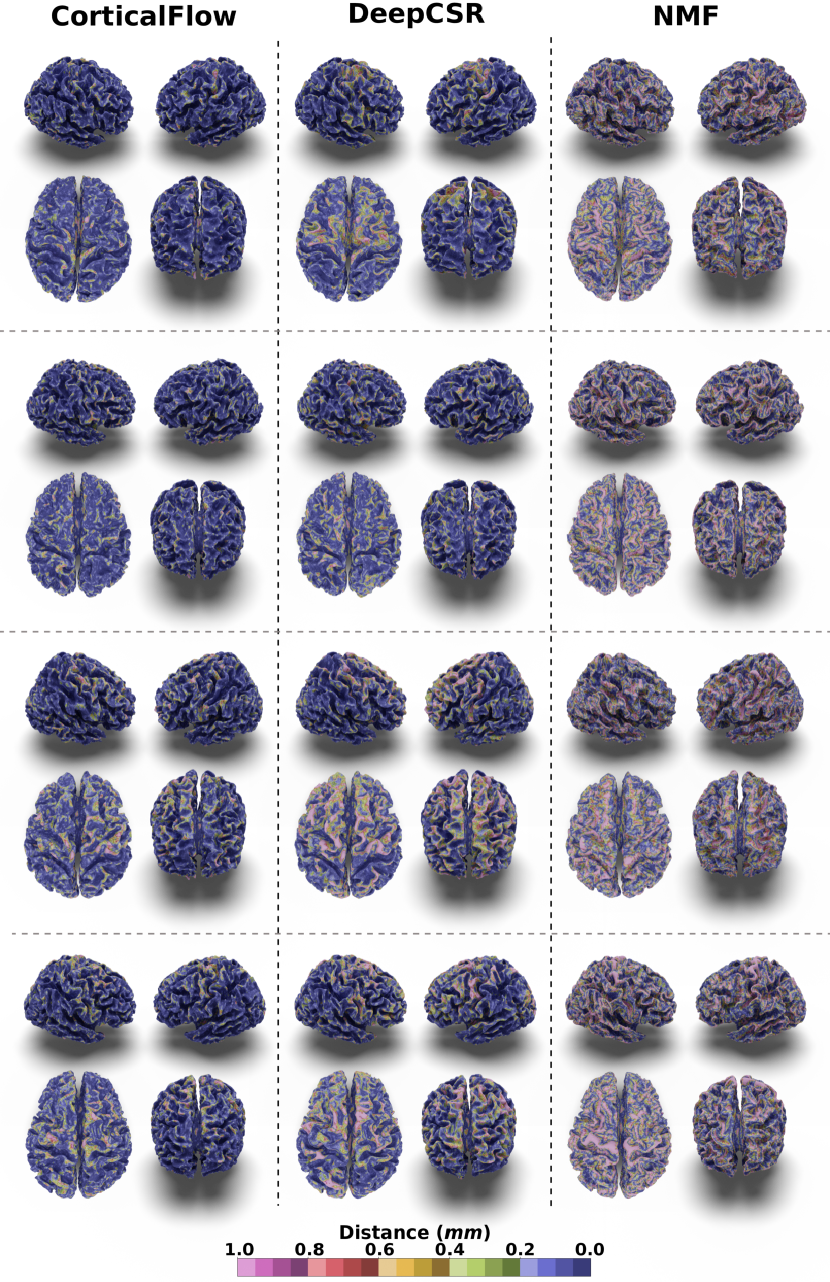

In our experiments, we noticed that CorticalFlow produces more geometrically accurate surfaces than the other methods. On average, it presents better geometric metrics across all the cortical surfaces. In addition, as shown in Figure 3, CorticalFlow errors are smaller () and evenly spread across the surface compared to the other methods. In contrast, NMF and DeepCSR can present substantial errors (). The former has its error spread across the entire surface, while the latter can produce large errors at specific regions.

CorticalFlow also generates triangular meshes with better properties than the evaluated methods. Compared to the deformation-based methods NMF and Voxel2Mesh, CorticalFlow predicted meshes are genus-zero surfaces and present a lower percentage of self-intersecting faces (mainly for the inner cortical surfaces). Figure 5(a) presents examples of self-intersecting faces produced by CorticalFlow, which are contrasted with the NMF predicted mesh for the same input MRI. The implicit-surface-based DeepCSR method does not produce a single self-intersecting face since it employs computationally expensive post-processing routines like topology correction [4] and iso-surface extraction. However, these post-processing routines do not take into account the input MRI which can generate non-plausible corrections on the output mesh as previously observed in Segonne et al. [67] and exemplified in Figure 5(b). Similarly, the voxel-wise segmentation baseline (i.e., QuickNAT) is free of self-intersecting faces, but it does not produce genus-zero surfaces. Indeed, QuickNAT’s predicted surfaces are composed of multiple connected components presenting many handles and holes which is not acceptable for the purpose of cortical surface reconstruction. Some examples of QuickNAT reconstructed cortical surfaces are presented in our supplementary material. Therefore, we argue that CorticalFlow is the method of choice to reconstruct regular surfaces from volumetric images.

Comparison with DeepCSR and NMF